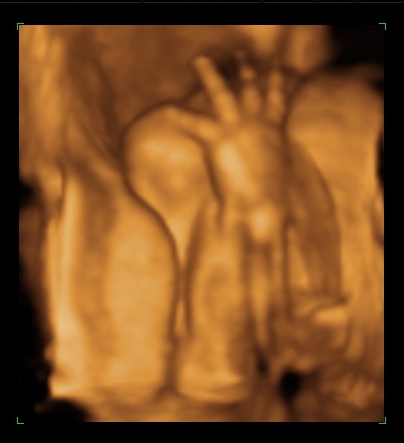

Rólunk: tegnap voltam a dokinál, nagy valószinüséggel kislány a Pötty babánk (de még nem mondta tutira a doki, mert eléggé összezárta a lábikóit)